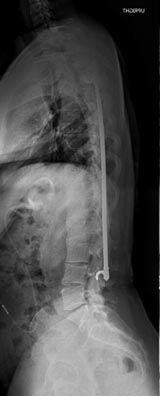

21 year old woman with very ridged 90 degree Scheuremann's kyphosis corrected to 40 degrees.